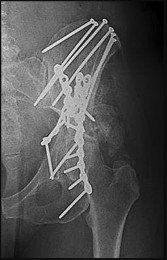

A 24-year-old male sustains a high-energy pelvic ring injury after a motor vehicle collision. CT imaging demonstrates a displaced crescent fracture of the ilium extending into the posterior aspect of the sacroiliac joint, consistent with a Day Type II lateral compression injury.

What is the most biomechanically stable method of surgical fixation for this specific posterior ring injury?

Explanation

Day Type II crescent fractures involve a major fracture line exiting the iliac wing, but a substantial portion of the posterior ilium remains attached to the sacrum via the posterior SI ligaments. Biomechanical studies have demonstrated that for Day Type II fractures (where the fracture extends into the SI joint), combining an iliosacral screw to stabilize the SI joint component with an orthopedic plate for the iliac wing fracture provides the most stable construct, superior to either method alone.